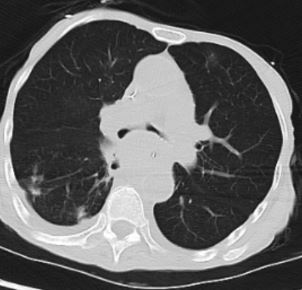

患者,81岁,因“胸闷、气喘4月,加重1天”急诊入院,入院时已因呼吸衰竭行气管插管呼吸机支持,病情凶险,患者既往确诊食管癌,近期复查提示疾病进展,已出现广泛肺转移、纵膈淋巴结重度肿大,进一步影像学及支气管镜检查证实,纵膈淋巴结肿大、肺转移病灶,病变已严重侵犯气管、隆突和左右主支气管,导致左右主支气管均出现重度狭窄,气道通畅度不足,随时可能因气道梗阻窒息死亡,且患者高龄、体质虚弱,给诊疗带来极大挑战。

2026年3月31日下午3时,在费卫东等麻醉团队密切配合下,先对患者进行全麻、肌松,呼吸介入专家俞小卫带领下,黄燕华、陈意、刘志光主任紧密配合,利用STOZE 成像系统引导,成功插入硬质气管镜鞘管,在高频通气保驾下,置入导丝,沿导丝插Y形支架到位后逐步释放支架,支架到位,最后采用球囊对支架进行扩张塑形,支架贴壁良好。